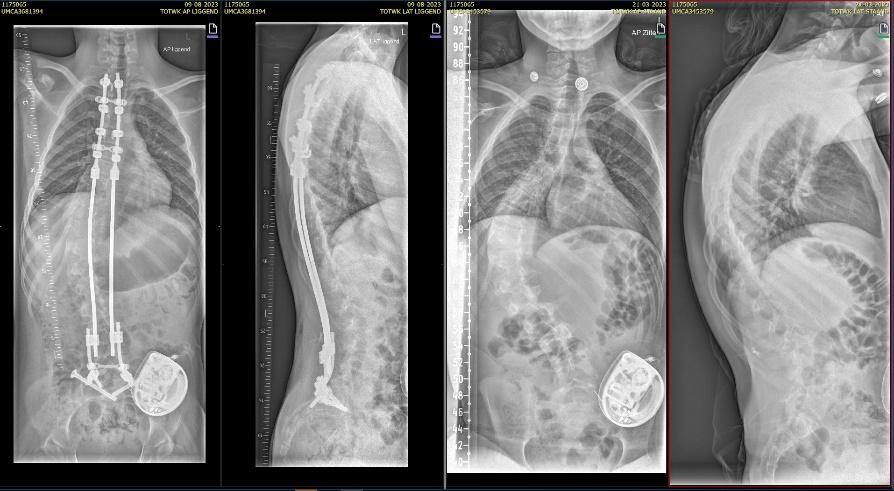

Als de voorbereidingen klaar zijn begint de operatie. De orthopedisch chirurg hangt kleine gewichtjes aan je benen en hoofd zodat je goed recht ligt. Hiervoor plaatsen we een klem net boven je oren, na de operatie is deze weer verwijderd maar heb je twee kleine gaatjes.. De orthopedisch chirurg maakt een of twee wond(en) op de rug. Tijdens de operatie maakt de chirurg de bocht in jouw wervelkolom zo recht mogelijk. De wervelkolom wordt vastgezet met behulp van titanium staven (of kobalt chroom) en schroeven of haakjes.

Bij neuromusculaire scolioses wordt er over het algemeen gekozen voor een “bipolair systeem”

Bij deze operatie zetten we de wervelkolom vast door middel van 2 verankeringspunten aan de ruggenwervels, boven tussen de schouderbladen en onder in het bekken. Hiervoor maken we een wond tussen de schouderbladen, onderin bij de lage rug, en ter hoogte van het bekken 2 kleine wondjes. De twee verankeringspunten verbinden we met elkaar door een metalen staaf onder de huid te schuiven. Met de staven kunnen we de rug rechter maken.

Rontgen foto voor (links) en na (rechts) scoliose correctie

Controle röntgenfoto

Vlak voor je naar huis gaat maken we ter controle een röntgenfoto van je wervelkolom om te controleren of de ankerpunten goed zijn geplaatst en hoe de correctie van de scoliose eruit ziet.